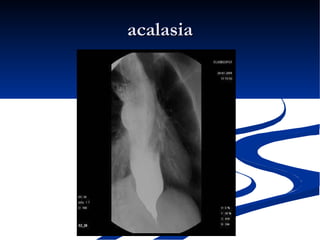

El documento habla sobre la anatomía y trastornos del esófago. Menciona las condiciones como el esófago de Barrett, el divertículo de Zencker, la acalasia y el cáncer de esófago, describiendo sus síntomas y tratamientos. Explica que el esófago de Barrett aumenta el riesgo de cáncer esofágico y que la acalasia se caracteriza por la hipertrofia del esfínter esofágico inferior y la ausencia de peristaltismo. También cubre factores de riesgo